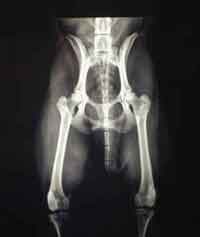

HD (Hüftgelenksdysplasie)

HD ist eine Fehlbildung der Hüftgelenke - das heißt Oberschenkelkopf und Gelenkpfanne passen nicht korrekt aufeinander. Diese Fehlbildung kann unterschiedlich ausgeprägt sein und tritt oft beidseitig auf.

Norberg Winkel

HD-Grade

Wir unterscheiden zwischen 5 verschiedenen Schweregraden der HD.

HD-frei - A

Das Gelenk ist absolut unauffällig und der Norbergwinkel beträgt 105 Grad oder mehr

HD-Verdacht/Grenzfall - B

Der Norbergwinkel beträgt 105 Grad oder mehr und die Gelenkpfanne und/oder der Schenkelkopf sind leicht ungleichmäßig oder aber Gelenkpfanne und/oder Schenkelkopf sind gleichmäßig, aber der Norbergwinkel beträgt weniger als 105 Grad

leichte HD -C

Norbergwinkel 100 Grad oder kleiner, ungleichmäßiger Oberschenkelkopf und Gelenkpfanne. Unter Umständen sind auch schon leichter arthrotischer Veränderungen zu bemerken.

mittlere HD - D

Norbergwinkel größer als 90 Grad und deutliche Ungleichmäßigkeiten von Oberschenkelkopf und Gelenkpfanne. Veränderungen des Pfannenrandes und/oder arthrotische Veränderungen sind zu erwarten oder schon vorhanden.

schwere HD - E

Norbergwinkel weniger ald 90 Grad, abgeflachter Pfannenrand, auffällige Veränderungen an Oberschenkelkopf und Gelenkpfanne. Deutliche arthrotische Veränderungen sind zu erwarten oder schon vorhanden.